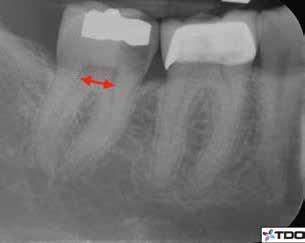

1. a–g. ábrák: A direkt pulpasapkázás lépései. Kiindulási bitewing-felvétel: A meglévő restaurátum közel helyezkedett el a pulpakamrához (a). Kiindulási periapicalis felvétel: Nincs periapicalis elváltozás fennállására utaló jel (b). A pulpaexpozíció (c). A vérzéscsillapítás céljából 20 másodpercen keresztül steril vattagombóccal történő kompressziót követően látható pulpaseb (d). A pulpasapkázás céljából behelyezett anyag, a széli részek tisztázása előtt készült felvétel (e). A röntgenárnyékot nem adó ideiglenes tömés behelyezése után készült felvétel (f). Az első ülés végén a röntgenárnyékot nem adó ideiglenes töméssel ellátott fogról készített röntgenfelvétel (g).

2. ábra: A hat hónapos kontroll alkalmával készített röntgenfelvételen vastag dentinhíd látható a pulpasapkázó anyag alatt.

3. ábra: A hároméves kontroll alkalmával készített röntgenfelvételen megfigyelhető a restaurátum pontos illeszkedése.

A kezelést követően a beteg tünetmentes volt. A kérdéses fog a kontrollvizsgálatok során végzett szenzibilitástesztekre fiziológiás reakciókat adott. A hat hónapos kontroll alkalmával készített röntgenfelvételen a sérülésnek megfelelően széles dentinhidat észleltünk (2. ábra). A restaurátum a hároméves kontroll során is megfelelőnek bizonyult (3. ábra)